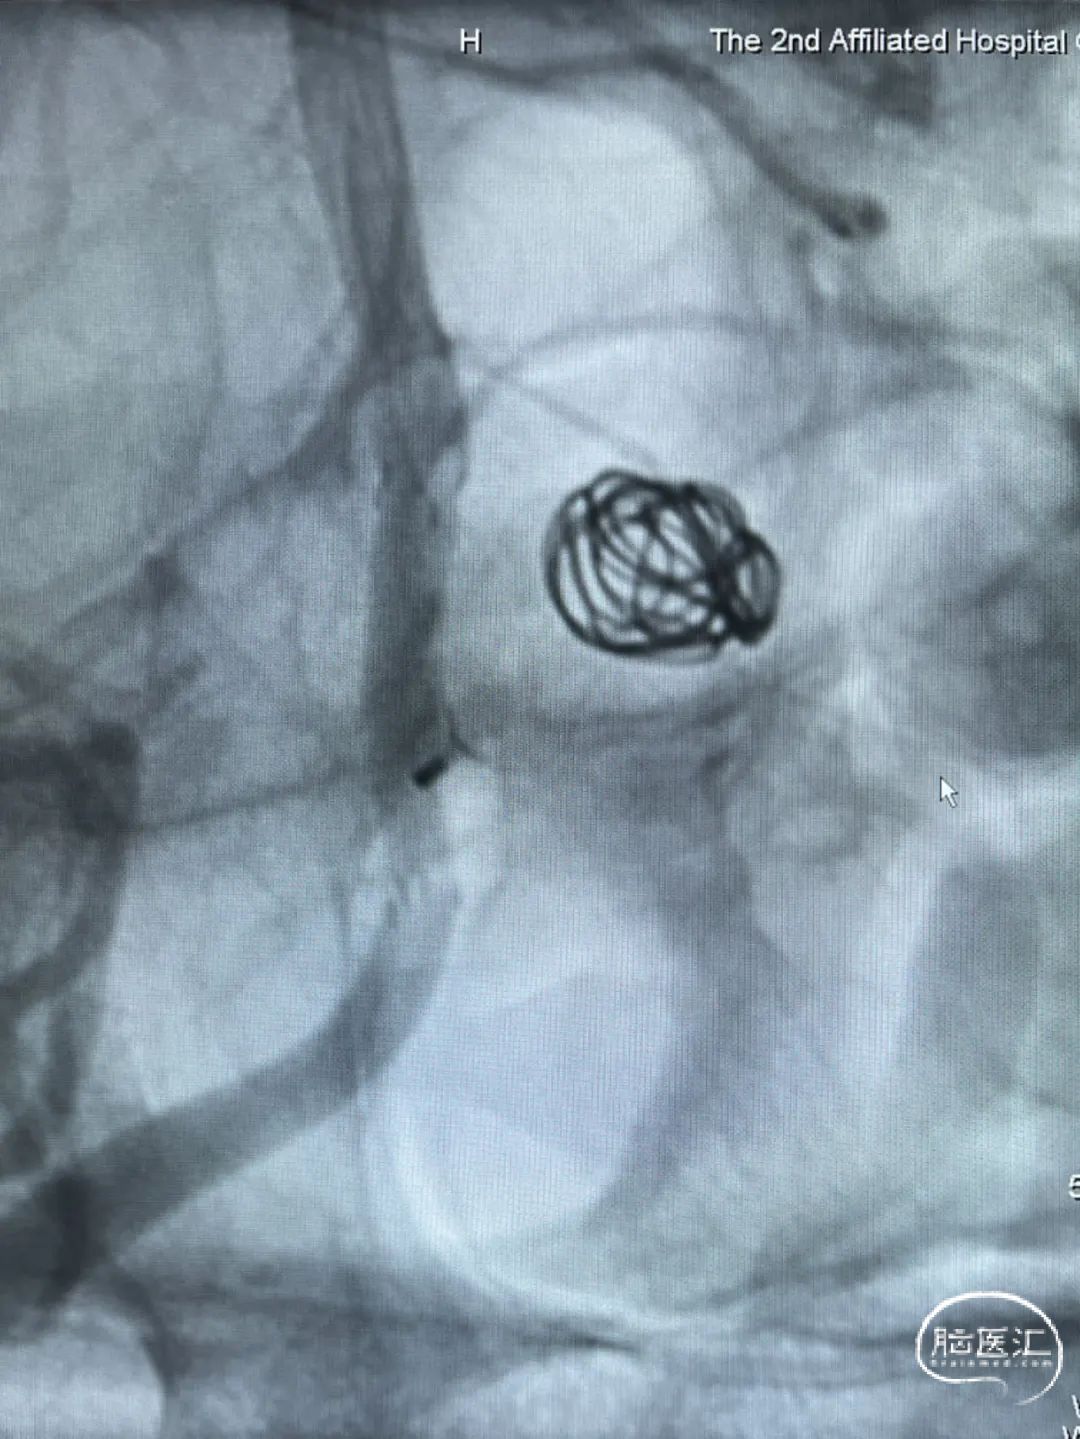

右侧后交通段动脉瘤,大小约13.36mm*13.26mm,瘤体上有子囊形成,床突段至后交通段血管稍狭窄,脉络膜前动脉距瘤颈部有一定距离。

Headway 17微导管塑形后置入动脉瘤瘤体内,半释放18mm*44cm complex弹簧圈成篮,半释放3.5mm*20mm LVIS支架保护瘤颈后完全释放18mm*44cm complex弹簧圈成篮,后依次释放6枚弹簧圈栓塞动脉瘤,最后一枚弹簧圈释放完成后造影,后交通动脉瘤少量造影剂进入,完全释放支架,右侧后交通动脉瘤瘤体内极少量造影剂进入,子囊不显影,Raymond分级3级,同时造影见各主干级分支血管显影良好,遂退出系统。

手术顺利,麻醉满意,术中生命体征平稳。

右侧后交通段动脉瘤完全闭塞。